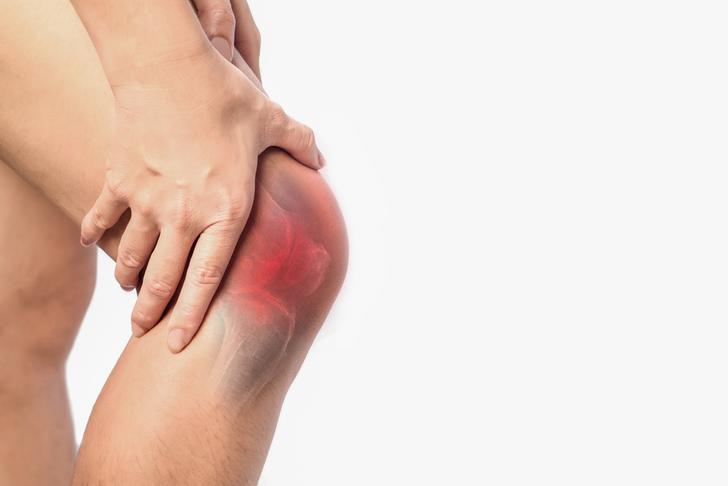

Swelling

Inflammation in the joints can cause swelling, which is another common symptom of osteoarthritis. This swelling may be more noticeable after periods of activity[[2]].